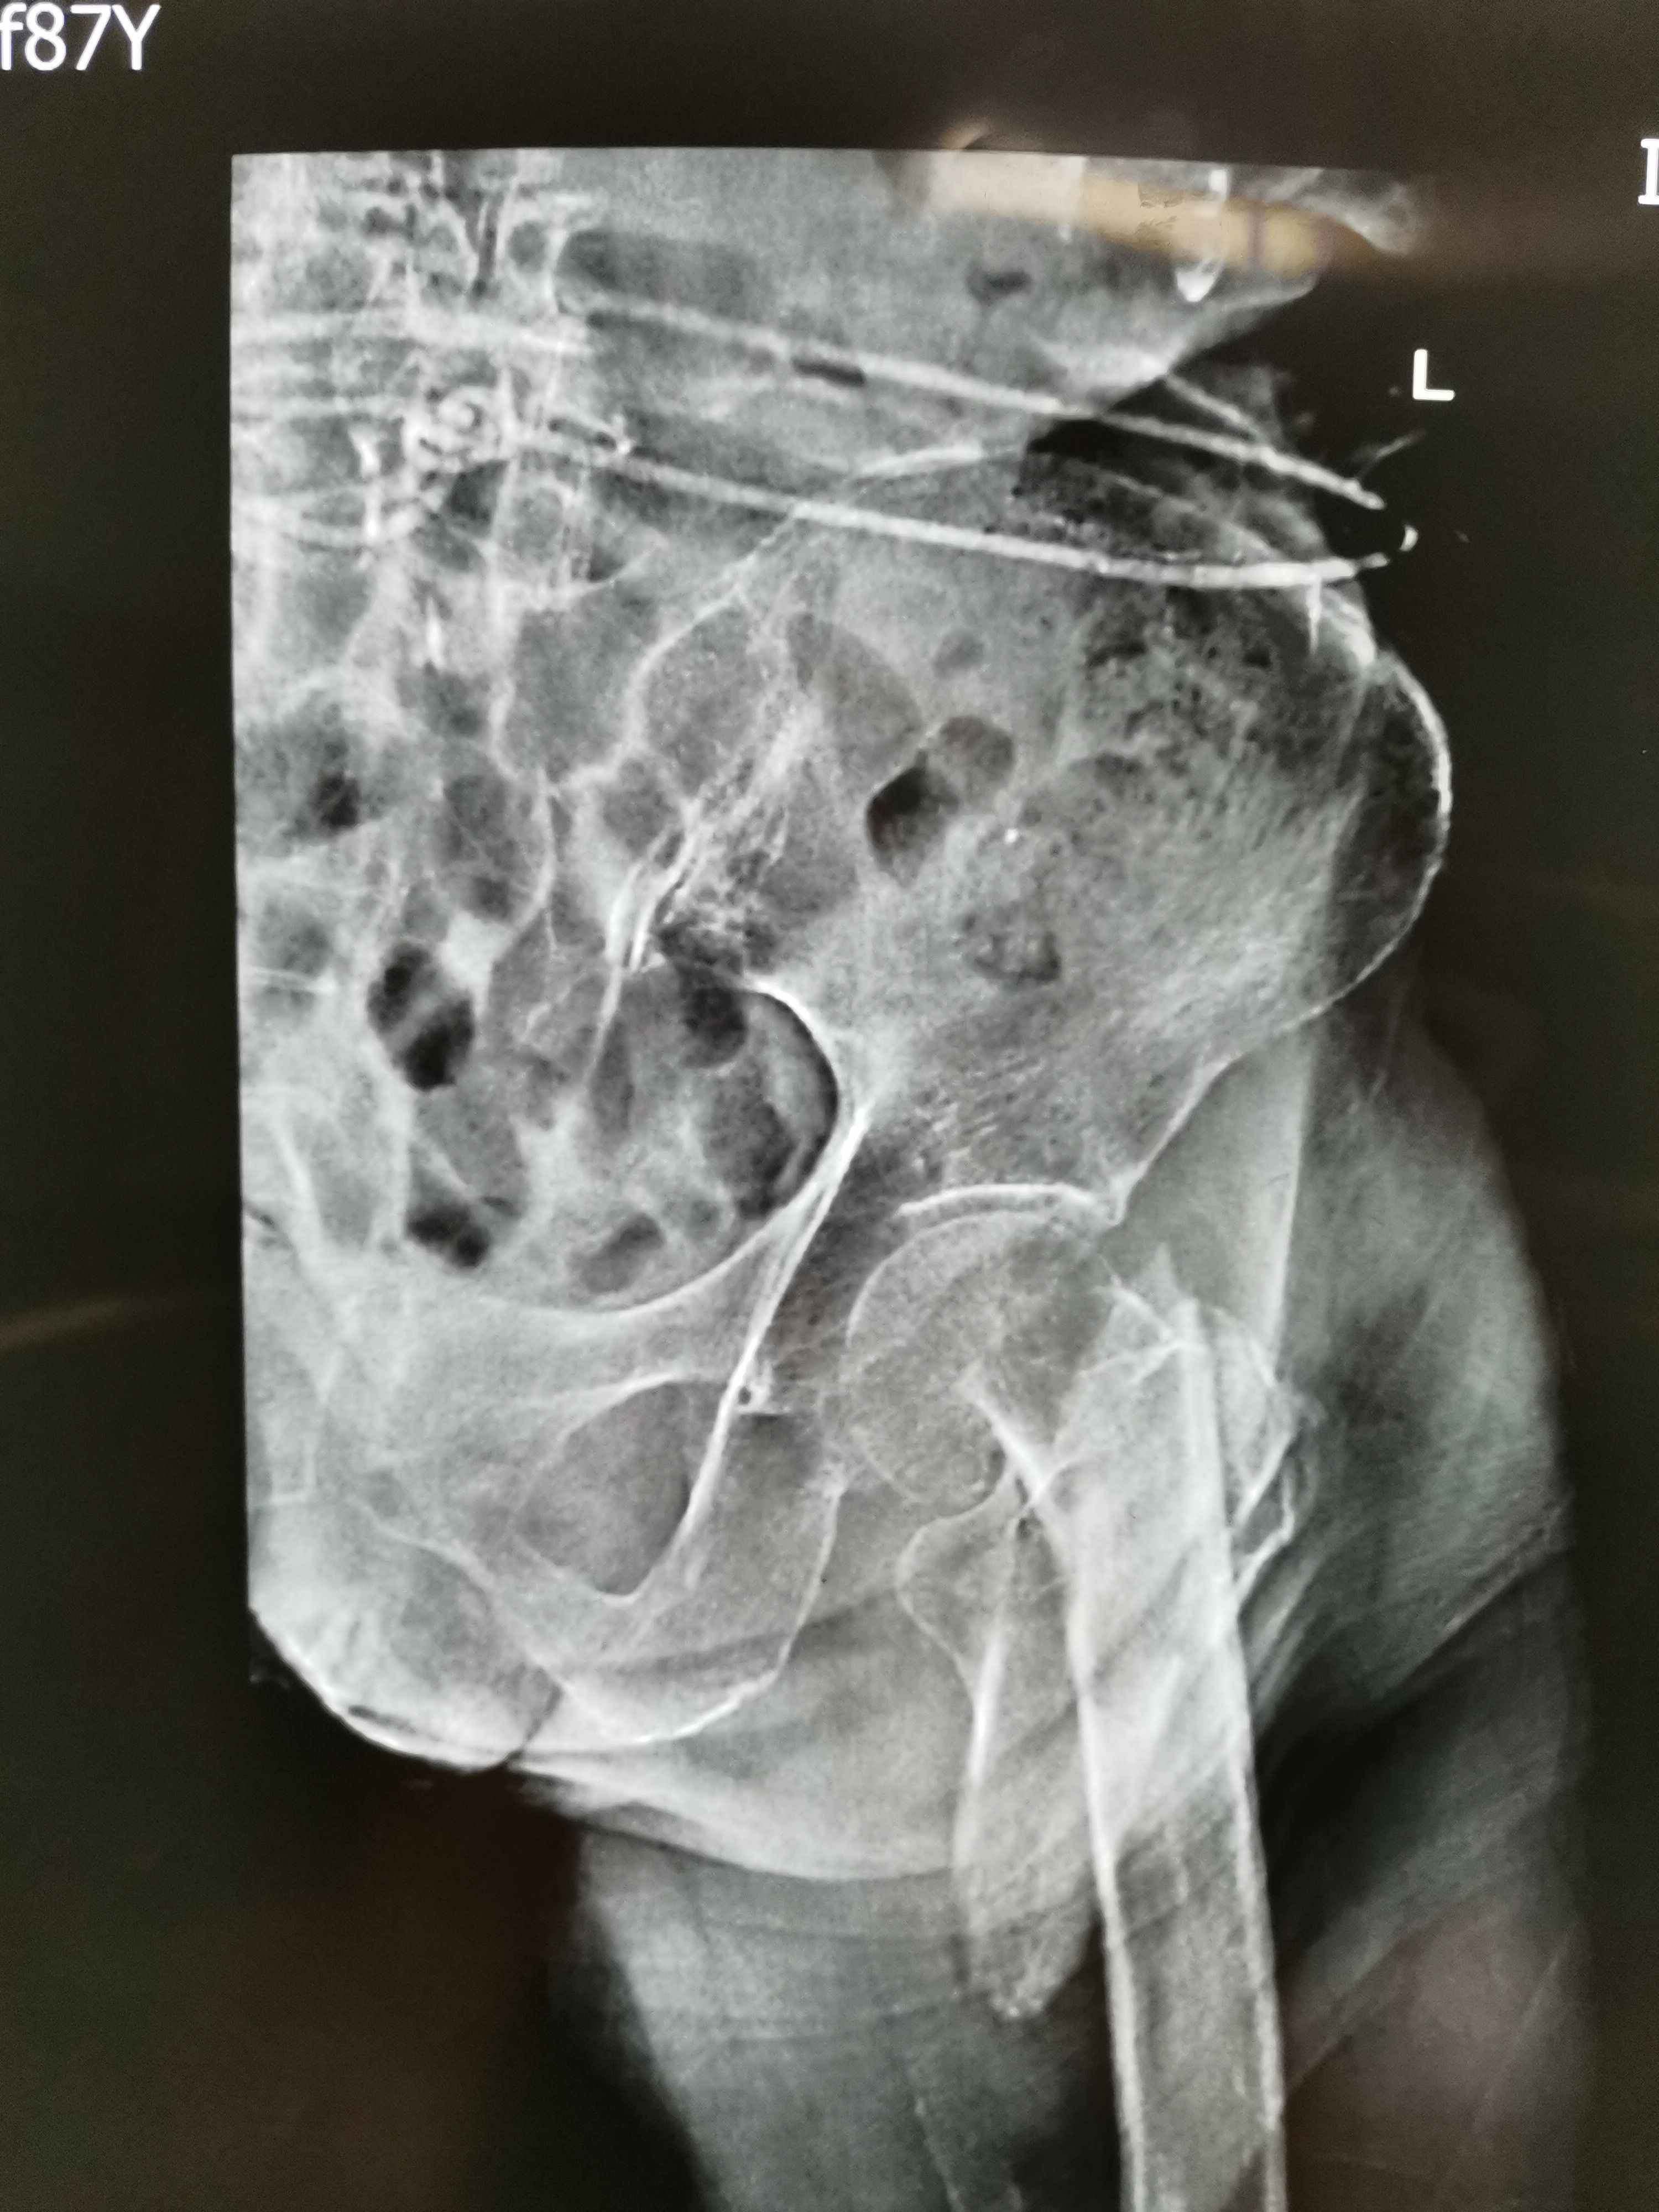

#清风计划#老人的X线片子如下:

左股骨粗隆间骨折

此X线的表现是一个左侧的股骨粗隆间骨折,断端在股骨粗隆下(科普需要,不再细分为股骨粗隆下骨折),呈粉碎性骨折,手术难度比较大,我们放大了来看一下:

- 1、诊断是明确的:左股骨粗隆间骨折,粉碎性,骨质疏松严重;